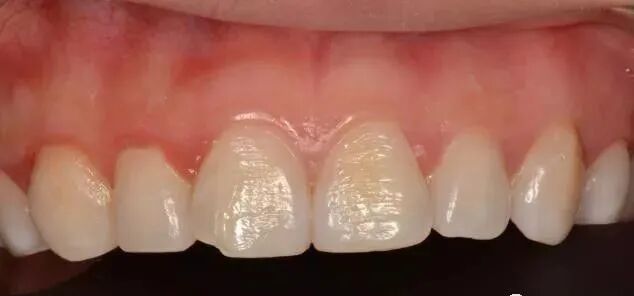

4、牙齒形態、色澤將直接影響面部的美觀,尤其是前牙缺損,補牙能恢複牙齒的自然形態和美觀,消除人們的因缺牙造成的自卑心理。

恢複牙齒的自然形態。牙齒的色澤、形態直接影響面部的美觀,尤其是前牙的形態對人的心理、情緒有至關重要的作用。

複合樹脂,接近牙齒顔色的填充材料,粘接性還不錯,特別耐磨抗腐蝕,關鍵補牙後還看不出有補過痕迹,大人和小朋友都可以使用。